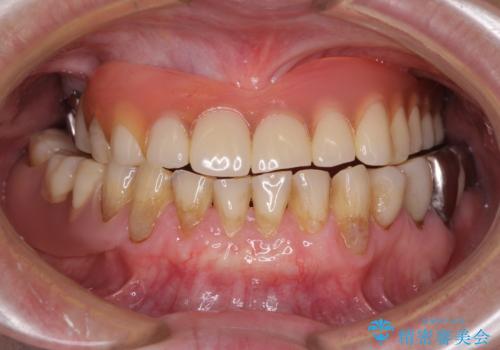

- 咬み合わせにより下の前歯の歯肉が退縮してしまい、根が見えていることが気になるとのことで来院された患者様です。

歯肉退縮に対して、上顎からの結合組織移植術(CTG)により、歯根の被覆を行うとともに、歯肉の厚みを増すことで将来の退縮リスクを抑制することとしました。

歯肉が大変薄かったため、歯肉移植による根面被覆の効果はそれほど高くないように思われましたが、想像以上に歯肉の位置を回復させることができました。

歯肉の厚みも十分に獲得でき、患者様には大変満足していただきました。